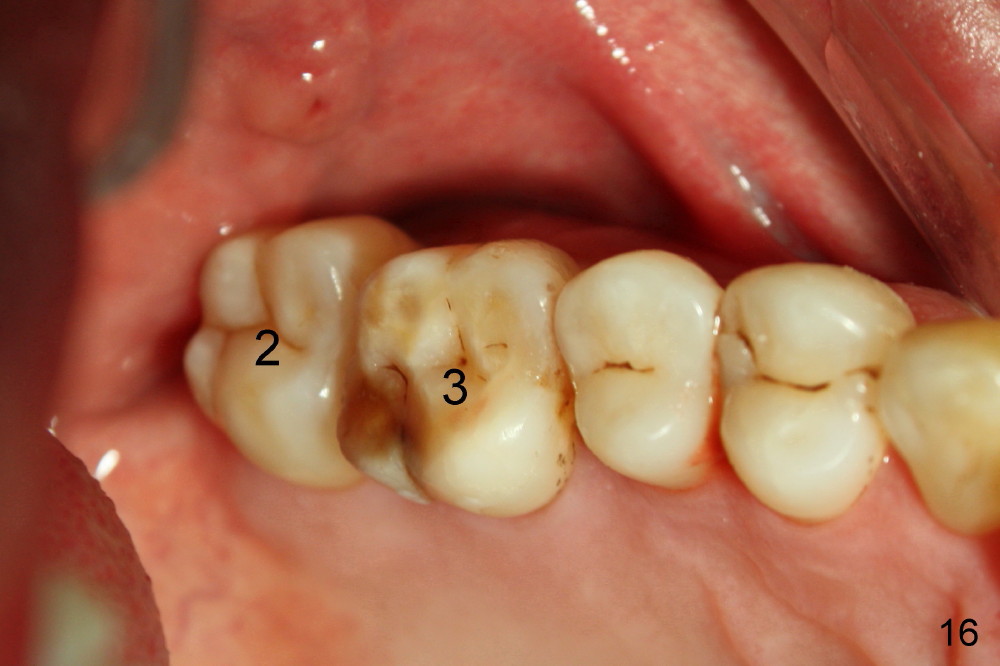

Fig.12-16 are taken 9 months after the orthodontic treatment. The lamina dura appears to form mesial and distal to the implant at the site of #30 (white arrowheads). There is no gross bone resorption associated with orthodontically moved teeth (Fig.12,13: #2,3,31). The posterior overjet remains normal (Fig.14). The arrowheads in Fig.15 indicate a worn facet, which was caused by the previous abnormal overjet (Fig.2). The alignment of the upper right quadrant also remains normal. The patient wears suction down retainers. He is pleased with improvement of mastication.